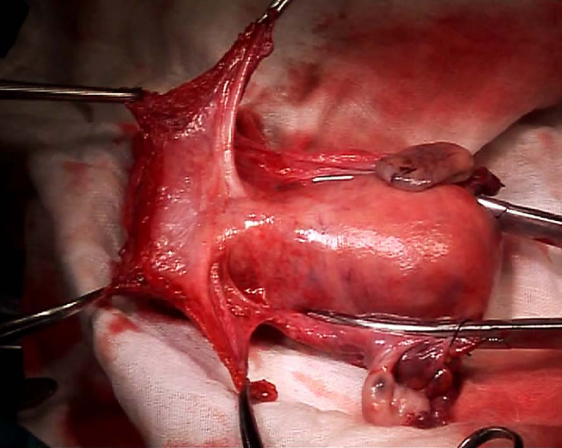

1.手术治疗 手术的优点是年轻患者可保留卵巢及阴道功能。主要用于早期子宫颈癌(ⅠA~ⅡA期)患者。①ⅠA1期:无淋巴脉管间隙浸润者行筋膜外全子宫切除术,有淋巴脉管间隙浸润者按ⅠA2期处理。②ⅠA2期:行改良广泛性子切除术及盆腔淋巴结切除术或考虑前哨淋巴结绘图活检(sentinel lymphnode mapping)。③ⅠB1期、和ⅠB2期ⅡA1期:行广泛性子宫切除术及盆腔淋巴结切除术或考虑前哨淋巴结绘图活检,必要时行腹主动脉旁淋巴取样。④部分ⅠB2期和ⅡA2期:行广泛性子宫切除术及盆腔淋巴结切除术和选择性腹主动脉旁淋巴结取样;或同期放、化疗后行全子宫切除术;也有采用新辅助化疗后行广泛性子宫切除术及盆腔淋巴结切除术和选择性腹主动脉旁淋巴结取样。未绝经、<45岁的鳞癌患者可保留卵巢。要求保留生育功能的年轻患者,ⅠA1期无淋巴脉管间隙浸润者可行子宫颈锥形切除术(至少3cm阴性切缘);ⅠA1期有淋巴脉管间隙浸润和ⅠA2期可行子宫颈锥形切除术加盆腔淋巴结切除术或考虑前哨淋巴结绘图活检,或和ⅠB1期处理相同;一般推荐ⅠB1期行广泛性子宫颈切除术及盆腔淋巴结切除术或考虑前哨淋巴结绘图活检,但若经腹或腹腔镜途径手术,手术指征也可扩展至ⅠB2期。

从左至右依次为Ⅰ、Ⅱ、Ⅲ及Ⅳ型子宫切除术的范围 Ⅰ型即筋膜外子宫切除术标本

Ⅲ型即广泛子宫切除术标本 盆腔淋巴结切除术标本

广泛子宫颈切除术切除的子宫颈及宫旁组织 广泛子宫颈切除术后功能重建的子宫及双附件